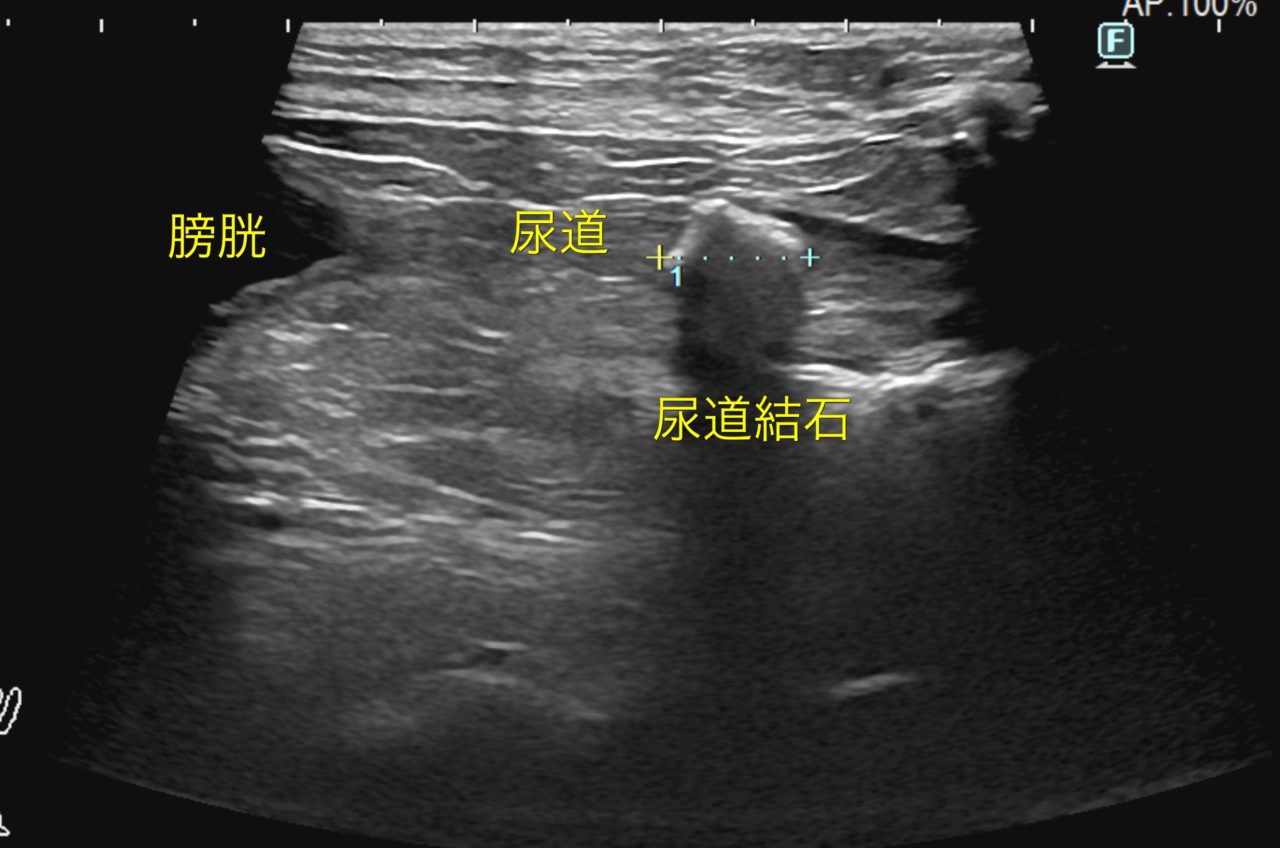

雌犬の尿道結石

尿道結石と電話がかかってくればまず、雄猫か雄犬を想像します。しかし、雌犬にも尿道結石は起こります。(頻繁ではありませんが)雌犬が尿道結石で苦しんでいるのでなんとかして欲しいと主治医より連絡がありました。エコーで見ると尿道結石が骨盤の手前でスタックしています。なるべく骨盤を切開しないで済む方法を考えました。まず、会陰切開を行い膀胱鏡を尿道内に侵入させたらどうか?無事にこの処置により運良く膀胱内に結石が脱落しました。その後、腹部に小切開を加え膀胱切開ののち尿結石を除去しました。成分はストラバイトと診断されたので今後は療法食を食べながら結石を予防します。雌犬でも運が悪いと結石により尿道閉塞を起こすので注意が必要です。